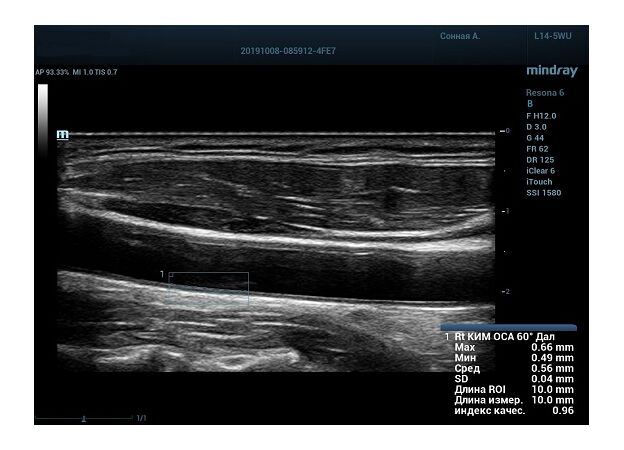

На сегодняшний день измерение IMT происходит автоматическим путем при использовании функции AUTO-IMT. Необходимо указать прибору зону интереса, стандартной длиной (1 см), в которой происходит отслеживание кромок и выдача максимального, среднего и минимального значения. УЗИ аппараты компании Mindray среднего, экспертного и премиального класса снабжены данной функцией и позволяют контролировать не только полученные значения, но и оценить точность измерения кромки в конкретной зоне по индексу качества. Используя индекс качества, легко решить, можно ли использовать полученное значение.